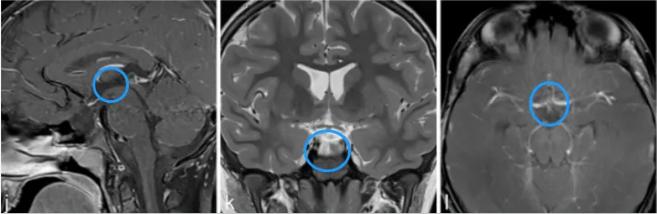

距离手术完成已过去两年时间,小宇坚持定期复查,影像学检查结果显示肿瘤无复发迹象,其身体状况持续好转。虽然目前仍在接受规范的激素替代治疗,但他已能够如同正常儿童般上学与玩耍,体重逐步恢复,身高也开始缓慢增长,面容重现灿烂笑容。